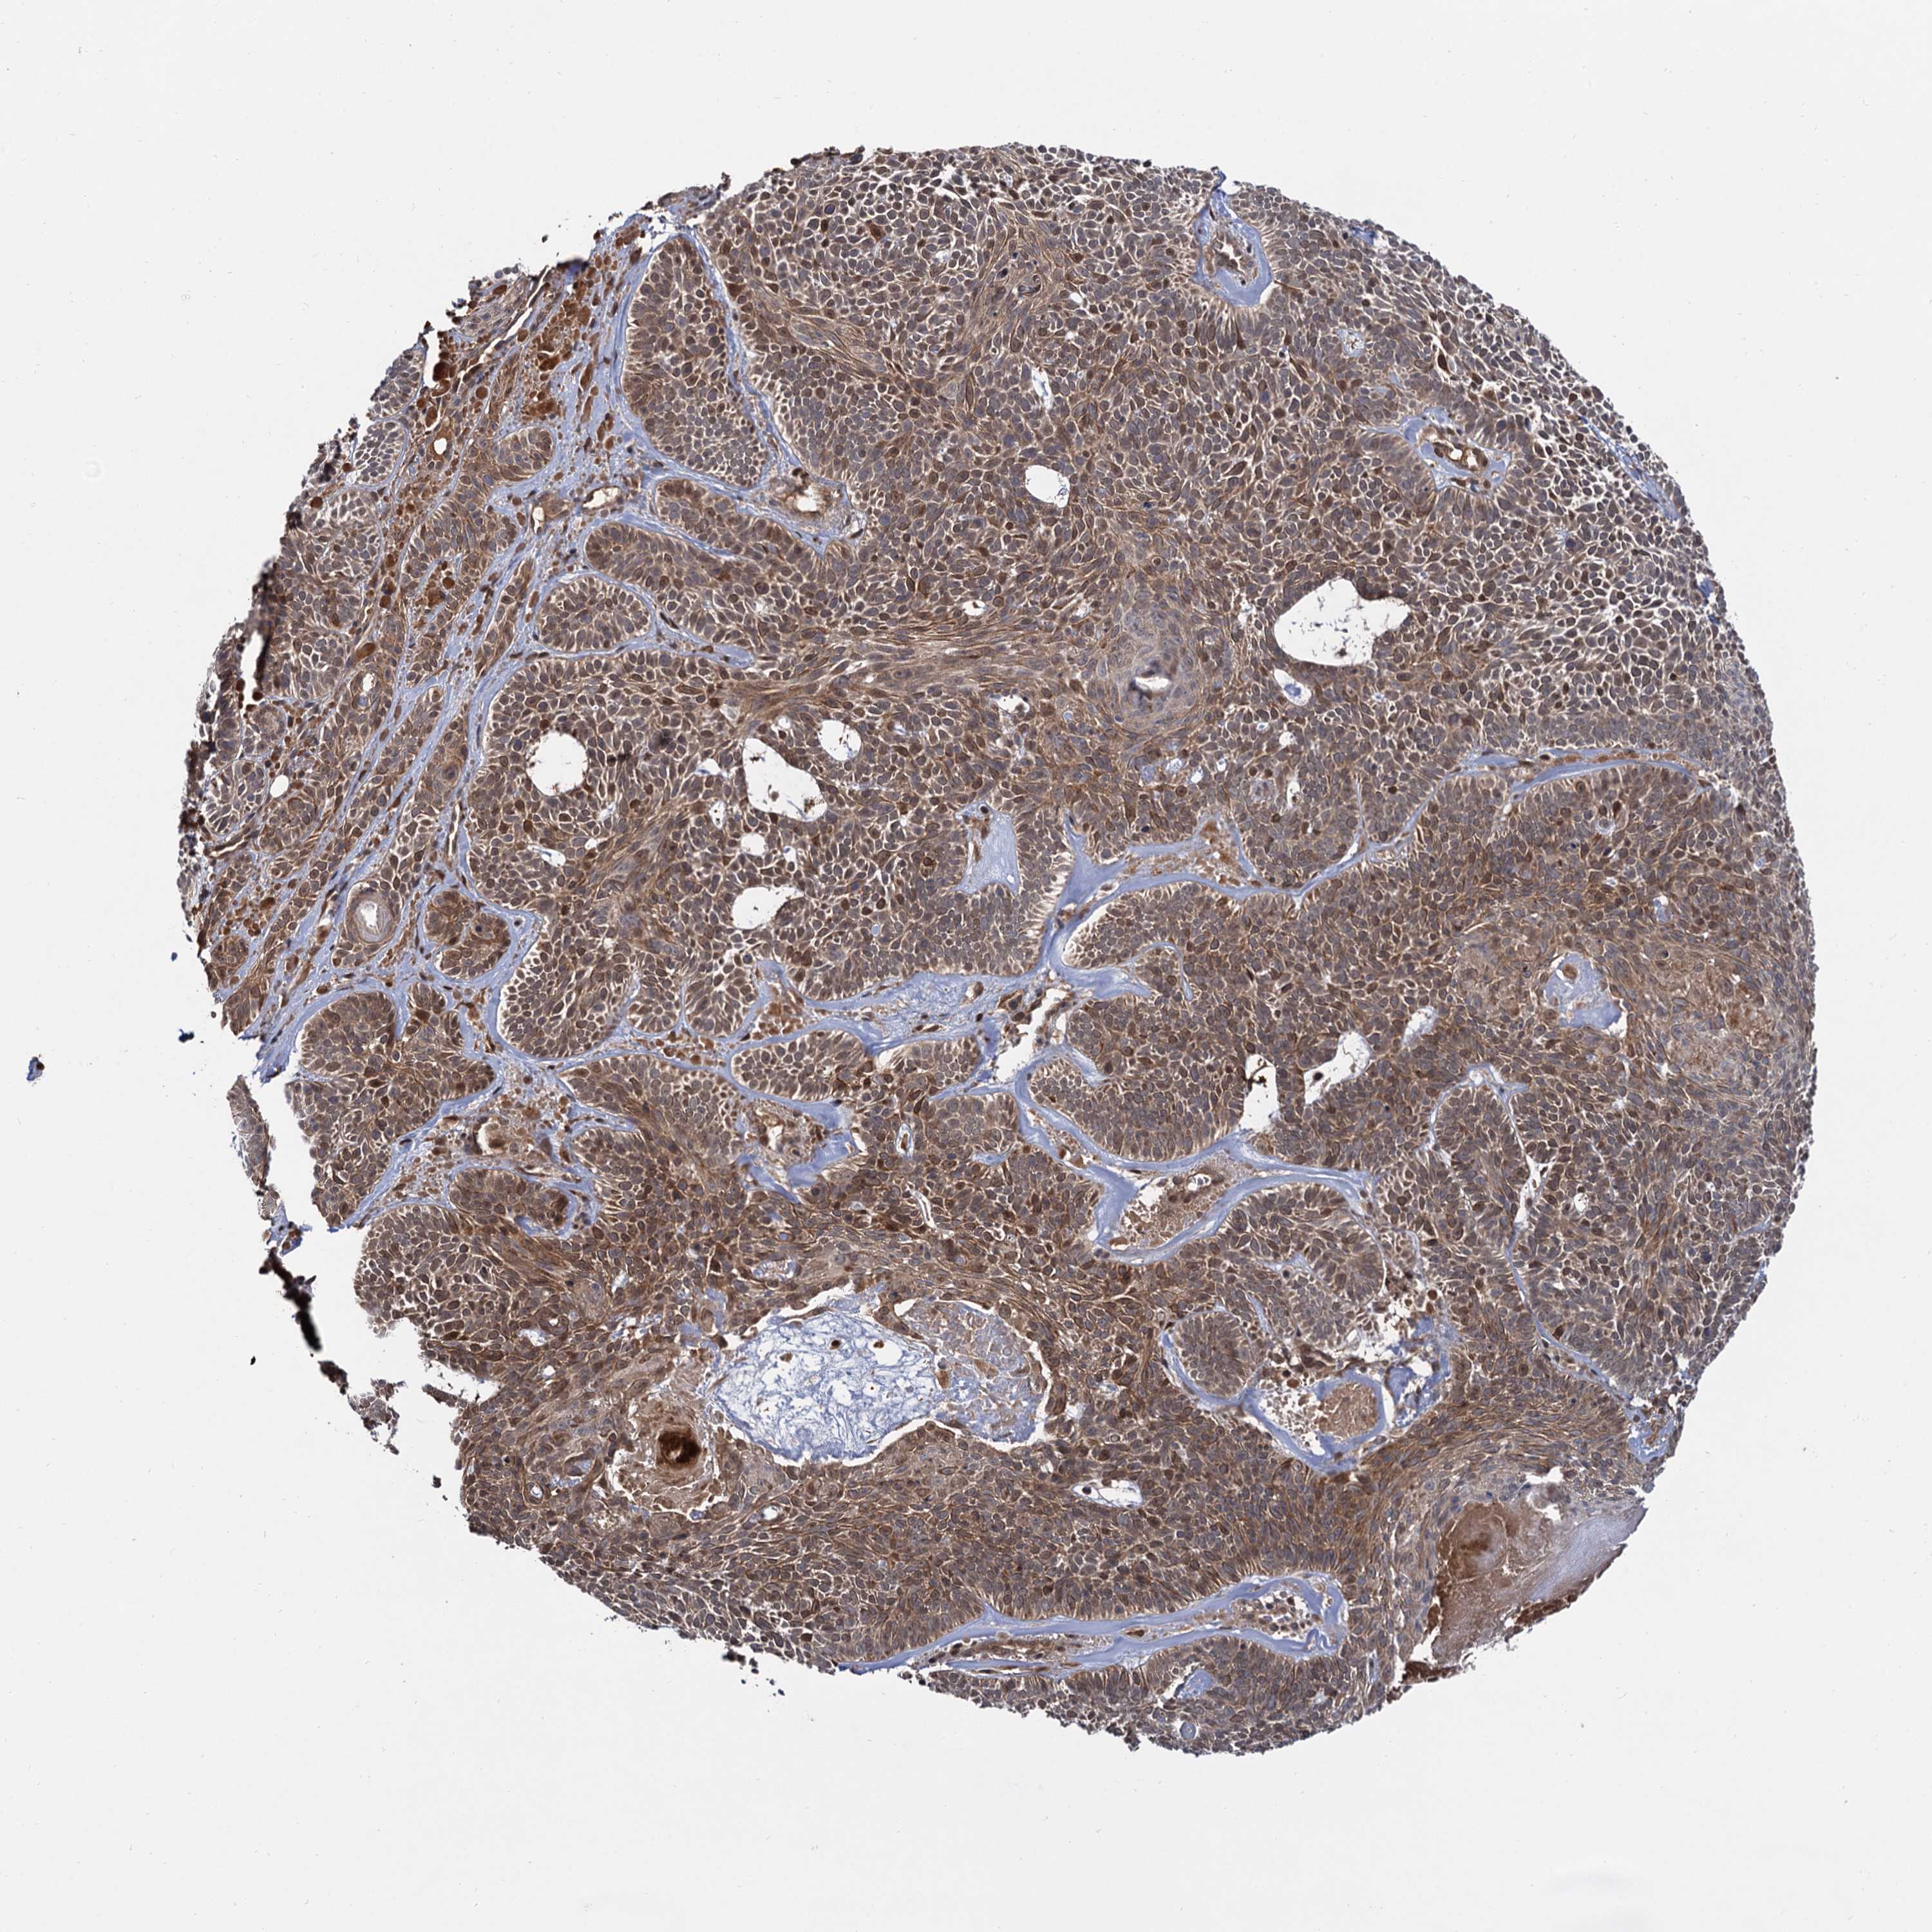

SKIN CANCER - Protein expressioni

A mouse-over function shows sample information and annotation data. Click on an image to view it in a full screen mode. Samples can be filtered based on level of antibody staining by selecting one or several of the following categories: high, medium, low and not detected. The assay and annotation is described here.

Antibody stainingi

Antibody staining in the annotated cell types in the current human tissue is reported as not detected, low, medium, or high, based on conventional immunohistochemistry profiling in selected tissues. This score is based on the combination of the staining intensity and fraction of stained cells.

Each image is clickable and will lead to virtual microscopy that enables deeper exploration of all samples and also displays staining intensity scores, fraction scores and subcellular localization as well as patient and tissue information for each sample.

Antibody HPA036287

Staining

High

Intensity

Strong

Quantity

>75%

Location

Nuclear

Basal cell carcinoma